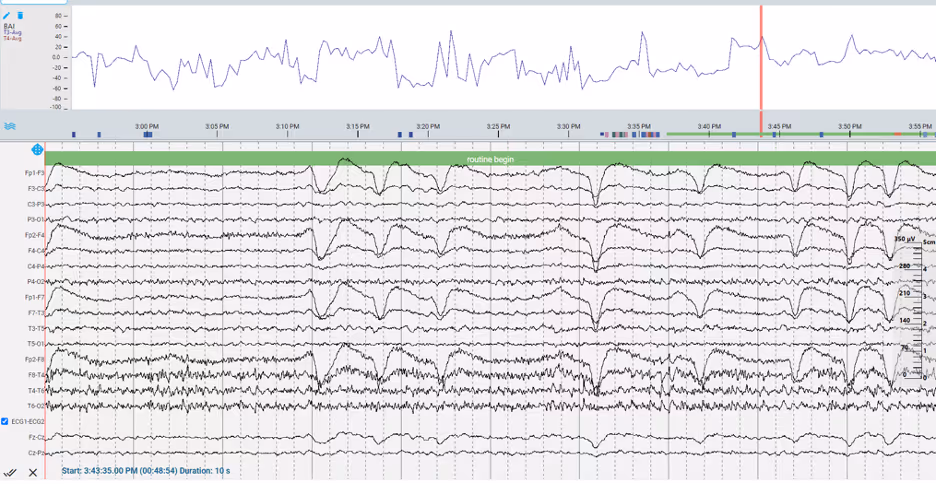

EEG Trends in Raw Data

Trends in Asymmetry

Clinicians can also look at the relative synchronicity between brain hemispheres to determine whether a pathological condition exists. Although healthy cerebral activity is not perfectly symmetrical, generally activity within the two hemispheres will be similar with only mild asymmetry. Trends, such as the amplitude asymmetry index (AAI) and brain symmetry index (BSI) measure the differences in activity between hemispheres and can be used to detect abnormality.